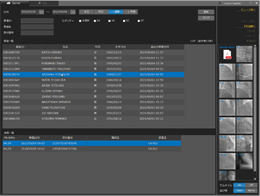

循環器向け動画像システム

自社開発の循環器科向けのDICOM規格準拠のPACSです。

X線アンギオ装置を始めとした各撮影装置からのDICOM通信によりDICOM画像の受信、保存をし、それらをネットワーク接続されたパソコンで動画像の再生等を行えます。

- マルティモダリティ対応(XA/US/IVUS/OCT/CT/MRI/CR/NM/DICOMPDF/SR等)

- 検査・患者一覧での高速な検索

- 患者情報、検査情報の編集、分割、マージ